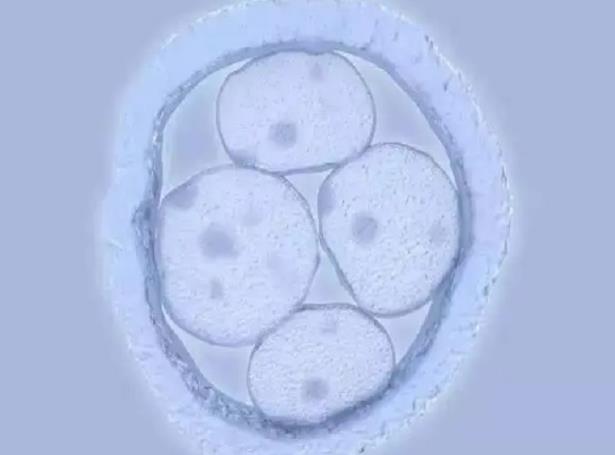

做试管婴儿除了要选择专业正规的医院之外,建议还要提前了解做试管婴儿的具体要求,尤其是要针对性调节身体体质,这样才能保证身体状态达到更好的标准,就算是自己生育能力有问题,但是也要在专业医生的指导状态下进行身体调理,这样才能更大程度的促进精子和卵子质量,从而让胚胎的结合效果更好。

网友经历